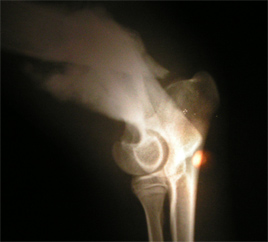

Sam hat einen schweren Bruch im rechten Vorderbein. Der Knochen ist gebrochen und gesplittert.

Sam´s Röntgenbild vom 02.10.07